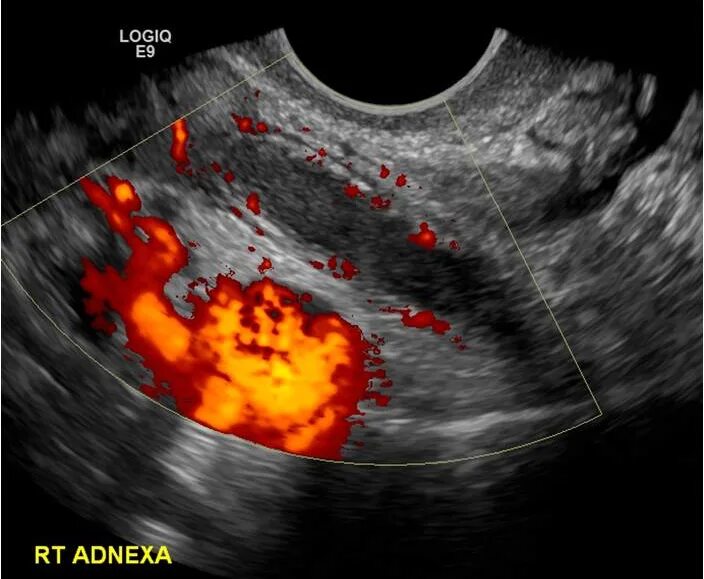

Аппендицит на узи можно ли